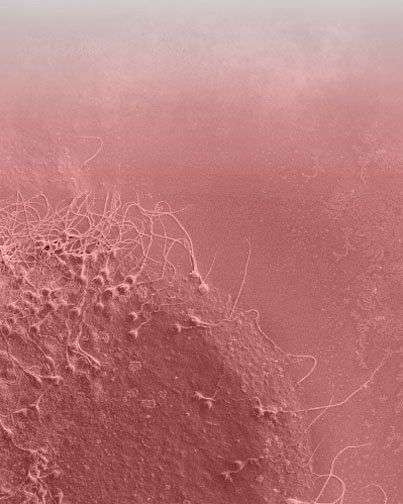

ИНДИВИДУАЛЬНОЕ ИССЛЕДОВАНИЕ РОДОВОДНОСТИ ДЛЯ ИНДИВИДУАЛЬНОГО ЛЕЧЕНИЯ